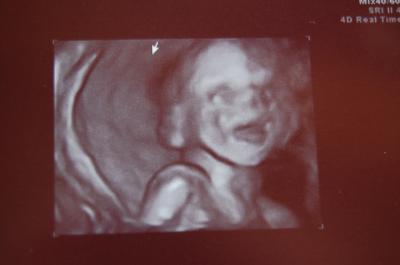

Hallo Mädels, oh man, wir haben gestern wieder mal was erlebt. Hatte die letzten zwei Tage auch immer wieder nen harten Bauch und so ein berühmtes Ziehen. Dachte mir erst nix dabei, da ich Samstag lang in der Küche stand, erst um zu kochen, dann noch um Kuchen zu backen und alles wieder wegzuspülen und zu verräumen und am Nachmittag hatten wir ja Besuch und selbst das Sitzen war sau... unangenehm (sorry für die Ausdrucksweise). Jedenfalls gings am Sonntag vormittag erst wieder und hab dann auch schön abgestaubt etc und dann hab ich schon gemerkt, Bauchi wird öfter hart, zieht auch öfter etc. Nun dachte ich, wenn ich abends am Sofa lieg wirds schon besser werden, aber pustekuchen irgendwie kam dieses "Ziehen" dann mehr als 3 mal die Stunde und schon seit zwei Tagen auch so das Gefühl in der Scheide als ob ein Tampon nicht richtig sitzen würde -> kennt das jemand von euch auch??? Hab dann auch bei der Hebamme nen Beitrag reingesetzt und direkt den Rat gekriegt das Gynäkologisch klären zu lassen. Und wie ICH halt so bin, ging mir das nimmer aus dem Kopf, wusste nicht ob ichs Montag früh anstehen lassen kann oder ob gleich zum Notdienst. Hab dann so ne innere Unruhe entwickelt, die mich dann dazu "trieb" meine Hebi anzurufen, die meinte auch, ne fahr lieber mal ins KH und lass es klären. Bin dann gleich gefahren und die waren dort auch recht nett. Die Ärztin hat erst den MuMu getastet - zu! - Gottseidank, dann noch den Gebärmutterhals mittels Ultraschall vermessen -> 44mm! Supi! Da fiel mir schon ein riesen Stein vom Herzen. Nach meinem Süßen hat sie dann auch gleich noch geschaut und sich auch richtig Zeit gelassen beim Schall - hab schon richtig Angst gekriegt - bis sie meinte:" man sind das super US-Bedingungen bei Ihnen, da könnte man ja "stundenlang" schallen - total interessant..." ob ich nen FD hätte machen lassen, das verneinte ich dann, sie nur drauf: mensch da wären Sie die perfekte Kandidatin dafür und ein absolutes Vorzeigemodell ;-) hihi, na supi. Jedenfalls meinte Sie, weil ich fragte ob sie mir den FD rät. "Ne, hab jetzt nochmal alles genau angeschaut und ist alles supi!" Sie hat auch das Geschlecht nochmal bestätigt - es bleibt unser Ben :-) und hat dann auch - AUSNAHMSWEISE, weil sie ja soo begeistert war, noch ein 3D Bild gemacht und mitgegeben - total süß, hängs gleich mit ran. Es war so richtig putzig. Er hat den Mund immer auf und zu gemacht. Man konnte sogar seine Zunge sehen und dann wars als wenn er gelächelt hätte - ein so genialer Schnappschuss. Achja und mein Süßer wiegt nun schon 440g! - WOW Naja, jedenfalls hab ich dann noch ein CTG gekriegt und da war aber glücklicherweise auch nix drauf zu sehen, in ner guten halben Stunde. Die Hebamme vor Ort meinte, es könnten tatsächlich auch die Mutterbänder sein, die auch bis in die Scheide ziehen. Ich hoffe ja mal dass sie da recht behält. Jedenfalls solle ich mich nun schonen - ja werde ich machen. Kenn das ja nun schon ;-). Dann hat heute meine Hebi angerufen und sich nach mir erkundigt (lieb ist) und hat mir nun geraten Bryophyllum 50% von Weleda zu nehmen 3xtgl. ne Msp voll und 2-3 Tassen Toko-Tee von I.Stadelmann und evtl. das Toko-Öl, aber nur vorsichtig und nur unten am Bauch, weil wenn man oben massiert oder streichelt kann das auch Wehen auslösen oder begünstigen. (Wieder was dazugelernt). So, nun sitz ich hier mit dem ganzen Reportoir (war heute nur kurz in der Apo) und mach jetzt das volle Programm, in der Hoffnung dass es hilft und Baby bitte bis zur 38.SSW mindestens im Bauchi bleibt. Ich rede ihm schon gut zu und seine Geschwister auch! :-) Sorry, dass es so lang war, aber musst mir das grad mal schnell von der Seele schreiben... Seid lieb gegrüßt, Michèlle & Ben inside (SSW 20+6)

Halloooo :) das ist ja mal ne lange Story hihi. Alsoo ich hatte diesselben Probleme gehabt :) dieses ziehen und allem drum und dran. ich konnnte ne zeitlang nich mal mehr gerade stehen geschweige den meine beine heben :x bin dann auch direkt zu meiner frauenärztin hab auch direkt ein Termin bekommen und bei mir war auch alles bestens und sie meinte auch das koennen diese Mutterbaender sein die sich dehnen und dann eine Art Muskelkater entfachen :) viel schonen und nich ueberanstrengen dann laeuft alles bestens :D und das Bild ist ja mal echt putzig :)) hast echt n süßen Krümmel :) Liebe Grüße Kristina + ( bis jetzt ein kleiner Prinz :D ) inside ! 20 SSW

freut mich, dass es euch beiden gut geht! und ich würde an deiner Stelle auch ins KH fahren, weil man sich sonst so noch reinsteigert, dass es auch nicht anders geht:)))) das Bild von eurem Ben ist ja echt goldig! LG Maria

Na du machst ja Sachen. Aber gut, dass alles in Ordnung ist und ganz toll, dass die Ärztin im KH sich soviel Zeit für dich genommen hat. Und nun schon dich etwas. Wau 440 gr sind echt viel. Ab 500gr gelten die Babys in Deutschland. Also wenn man es danach noch verliert, dann steht das aber irgendwo, dass man ein Kind hatte und es wird nicht einfach "unsichtbar". Und ein super Bild. Er lacht ja richtig da drauf. LG Sinsiria

Gut, dass Du das gleich hast abklären lassen! Ich hätte auch eine innere Unruhe entwickelt! Toll ist, dass sich die Ärztin so viel Zeitgenommen hat! 3D Bilder finde ich oft recht gruselig aber das von Ben ist ja echt der Hammer!! Wie wenn er lauthals lachen würde! Schön dass alles gut ist! Schon Dich ein bißchen! Alle Gute weiterhin, Bine

Ja ich finde auch dass die 3D Bilder zum jetztigen Schwangerschaftszeitpunkt wirklich oft sehr gespenstisch wirken, aber ich glaube ja dass unser Ben mal Model wird, so wie er es jetzt schon schafft sich in Szene zu setzen *lach*. Ich bin ja sooooooooooooooo verliebt in den kleinen Mann!!! Und wir reden ihm alle schon gut zu, dass er noch laaaaaaaaaaaaange im Bauchi bleiben soll. Mal sehen, sein nächstes "Fotoshooting" hat er dann in 2 1/2 Wochen wieder. Ich halte euch dann auf dem Laufenden! :-)